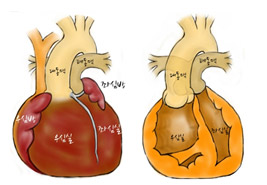

[그림3] 완전대혈관전위증 심장의 외부모습 / 내부모습

우심실과 대동맥이 연결되어 있고 폐동맥은 좌심실과 연결되어 있음